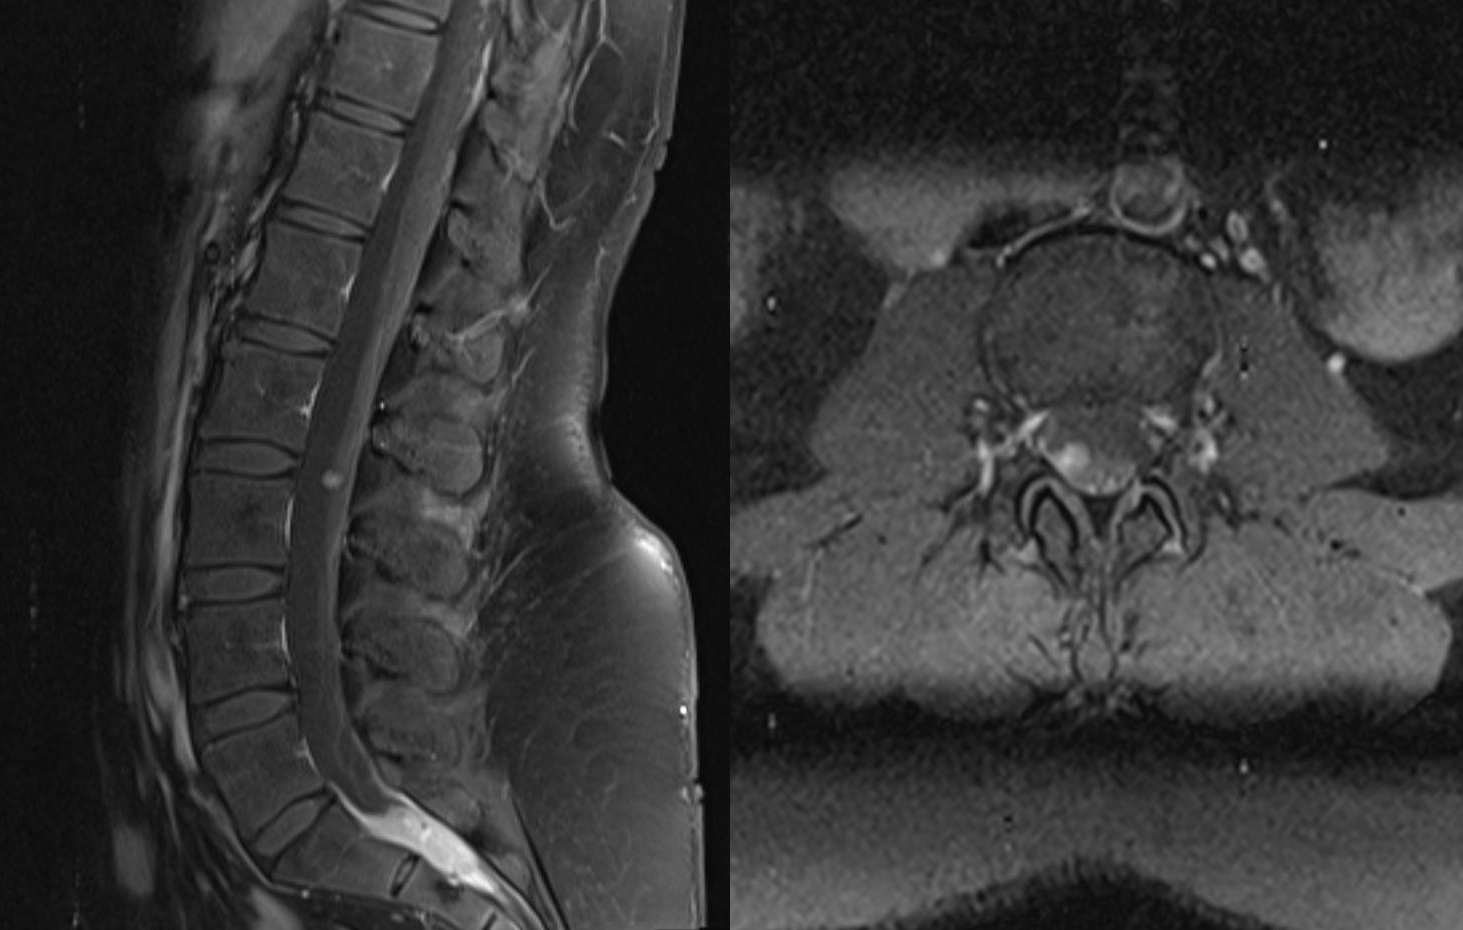

Zweitbefundung

Durch unsere universitäre Expertise bieten wir jedem eine kompetente Zweitbefundung seiner radiologischen Untersuchung.